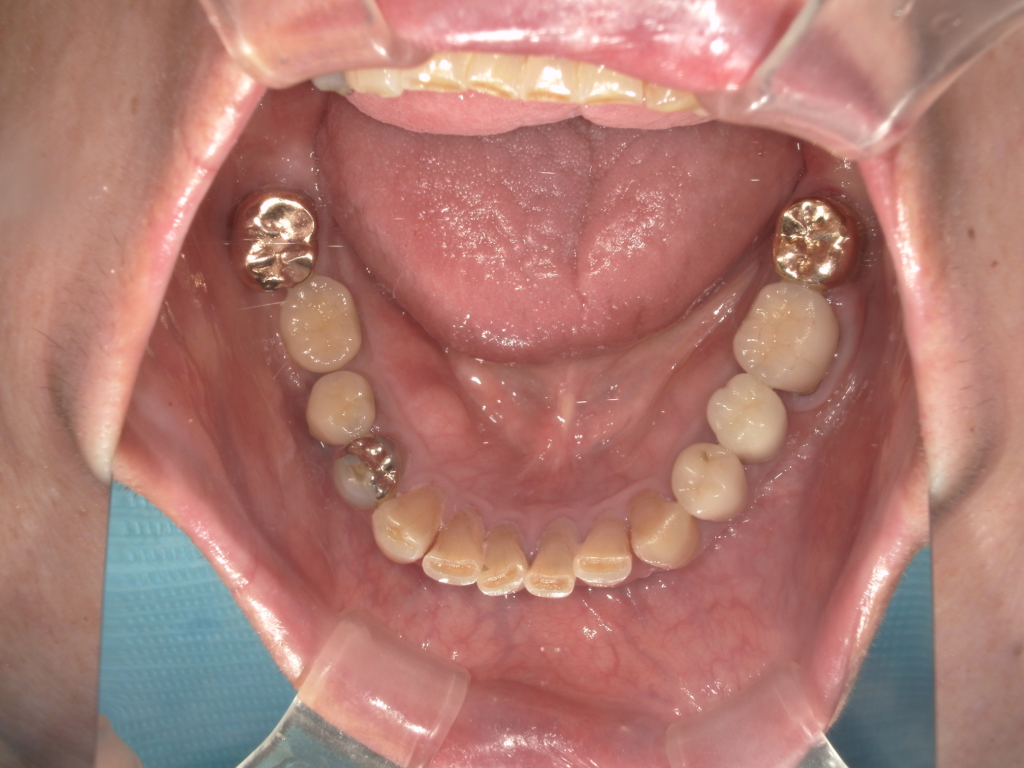

Y様インプラント実例 #44

左の上下の奥歯をインプラントで治療しています。

左下の奥歯は歯を抜くのと同時にインプラントの埋め込みを行っています。

被せものは上下、セラミックスで作っています。

治療前

治療後